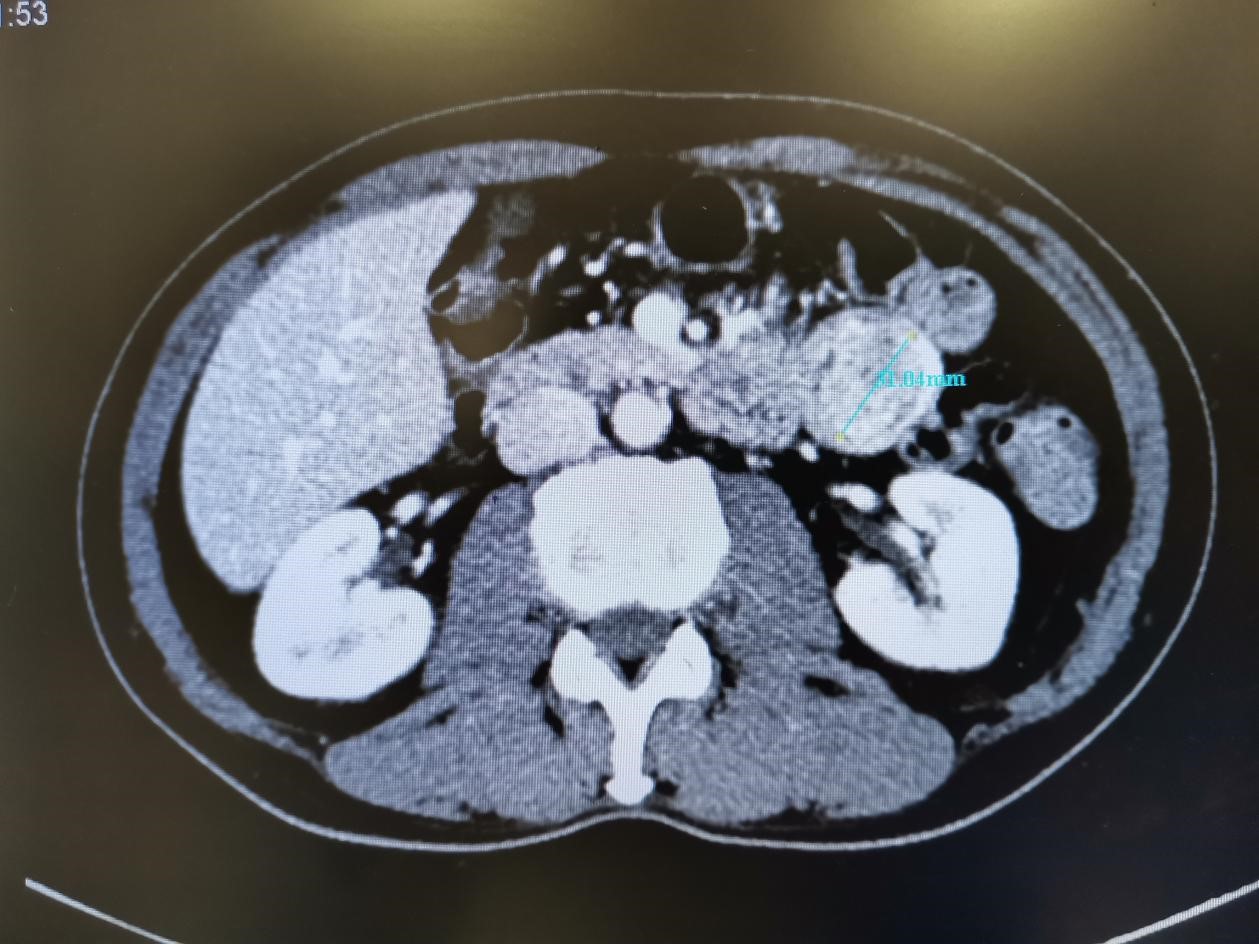

③腹部增强CT:十二指肠末端-空肠交界区肿块,考虑肿瘤性病变,间质瘤可能性大;增强后肿块旁及胃腔内高密度对比影,考虑出血。

行腹部增强CT排除静脉曲张性上消化道出血(VUGIB)后留置胃管

术中探查见:肿瘤位于十二指肠降段水平段交界处,大小约3*4cm